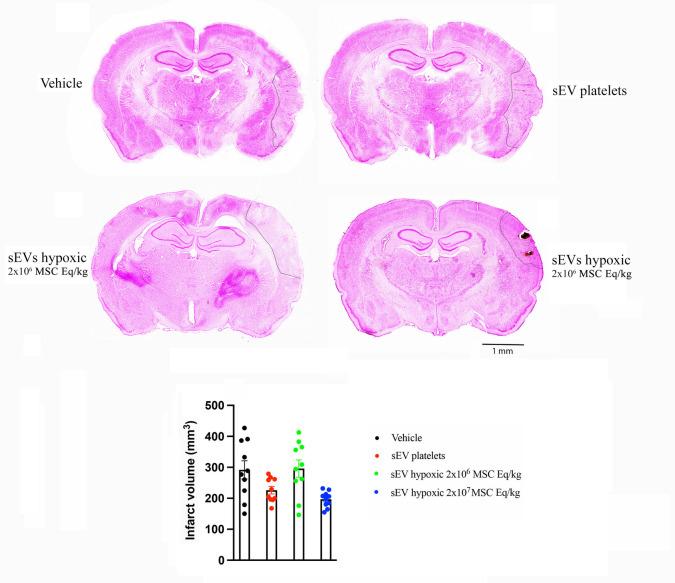

Small extracellular vesicles (sEVs) obtained from mesenchymal stromal cells (MSCs) have shown considerable promise as restorative stroke treatment. In a head-to-head comparison in mice exposed to transient proximal middle cerebral artery occlusion (MCAO), sEVs obtained from MSCs cultured under hypoxic conditions particularly potently enhanced long-term brain tissue survival, microvascular integrity, and angiogenesis. These observations suggest that hypoxic preconditioning might represent the strategy of choice for harvesting MSC-sEVs for clinical stroke trials. To test the efficacy of hypoxic MSCs in a second stroke model in an additional species, we now exposed 6-8-month-old Sprague-Dawley rats to permanent distal MCAO and intravenously administered vehicle, platelet sEVs, or sEVs obtained from hypoxic MSCs (1% O; 2 × 10 or 2 × 10 cell equivalents/kg) at 24 h, 3, 7, and 14 days post-MCAO. Over 28 days, motor-coordination recovery was evaluated by rotating pole and cylinder tests. Ischemic injury, brain inflammatory responses, and peri-infarct angiogenesis were assessed by infarct volumetry and immunohistochemistry. sEVs obtained from hypoxic MSCs did not influence infarct volume in this permanent MCAO model, but promoted motor-coordination recovery over 28 days at both sEV doses. Ischemic injury was associated with brain ED1 macrophage infiltrates and Iba1 microglia accumulation in the peri-infarct cortex of vehicle-treated rats. Hypoxic MSC-sEVs reduced brain macrophage infiltrates and microglia accumulation in the peri-infarct cortex. In vehicle-treated rats, CD31/BrdU proliferating endothelial cells were found in the peri-infarct cortex. Hypoxic MSC-sEVs increased the number of CD31/BrdU proliferating endothelial cells. Our results provide evidence that hypoxic MSC-derived sEVs potently enhance neurological recovery, reduce neuroinflammation. and increase angiogenesis in rat permanent distal MCAO.

从间充质基质细胞(MSCs)获得的小细胞外囊泡(sEVs)作为中风修复治疗已显示出巨大潜力。在对短暂性大脑中动脉近端闭塞(MCAO)小鼠进行的直接比较中,从在缺氧条件下培养的MSCs获得的sEVs特别有效地增强了长期脑组织存活、微血管完整性和血管生成。这些观察结果表明,缺氧预处理可能是收获用于临床中风试验的MSC-sEVs的首选策略。为了在另一个物种的第二个中风模型中测试缺氧MSCs的疗效,我们现在将6-8个月大的Sprague-Dawley大鼠暴露于永久性大脑中动脉远端闭塞(MCAO),并在MCAO后24小时、3天、7天和14天静脉注射载体、血小板sEVs或从缺氧MSCs获得的sEVs(1%氧气;2×10或2×10细胞当量/千克)。在28天内,通过转棒试验和圆筒试验评估运动协调恢复情况。通过梗死体积测量和免疫组织化学评估缺血性损伤、脑部炎症反应和梗死周围血管生成。在这个永久性MCAO模型中,从缺氧MSCs获得的sEVs不影响梗死体积,但在两种sEV剂量下均促进了28天内的运动协调恢复。缺血性损伤与载体处理大鼠梗死周围皮质中的脑ED1巨噬细胞浸润和Iba1小胶质细胞积累有关。缺氧MSC-sEVs减少了梗死周围皮质中的脑巨噬细胞浸润和小胶质细胞积累。在载体处理的大鼠中,在梗死周围皮质中发现了CD31/BrdU增殖内皮细胞。缺氧MSC-sEVs增加了CD31/BrdU增殖内皮细胞的数量。我们的结果提供了证据,表明缺氧MSC衍生的sEVs能有效增强神经恢复、减少神经炎症并增加大鼠永久性大脑中动脉远端闭塞模型中的血管生成。